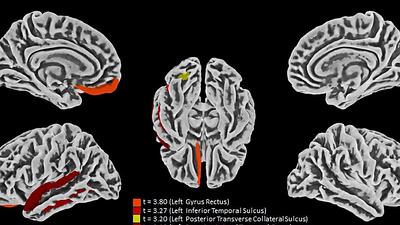

Um terço dos pacientes de covid-19 tem problemas neurológicos

Estudo brasileiro mostra como o coronavírus afeta o cérebro, causando de perda de memória a depressão e ansiedade. Sintomas podem acometer mesmo quem teve quadro leve da doença.